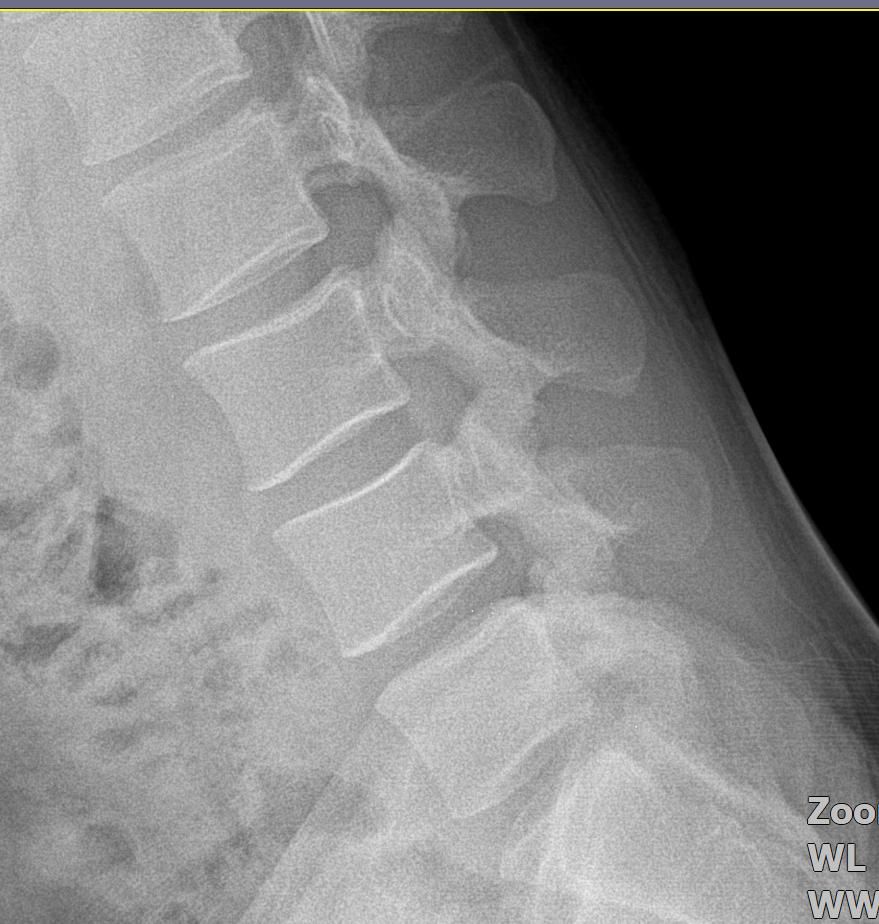

• 2번 째 사진

사진 공유해주신것을 보았을 때 뼈 모양 자체의 문제는 아닐 것으로 생각되며 반복적인 사다리작업으로 인한 근육의 과긴장 및 근육 및 근막의 문제로 인해서 그럴 수 있습니다.

신체 진찰이 필요하겠으나 올려주신 사진으로 미루어 척추 사이 간격은 잘 유지되고 있으나 정상적인 척추의 굴곡이 소실된 상태 입니다.